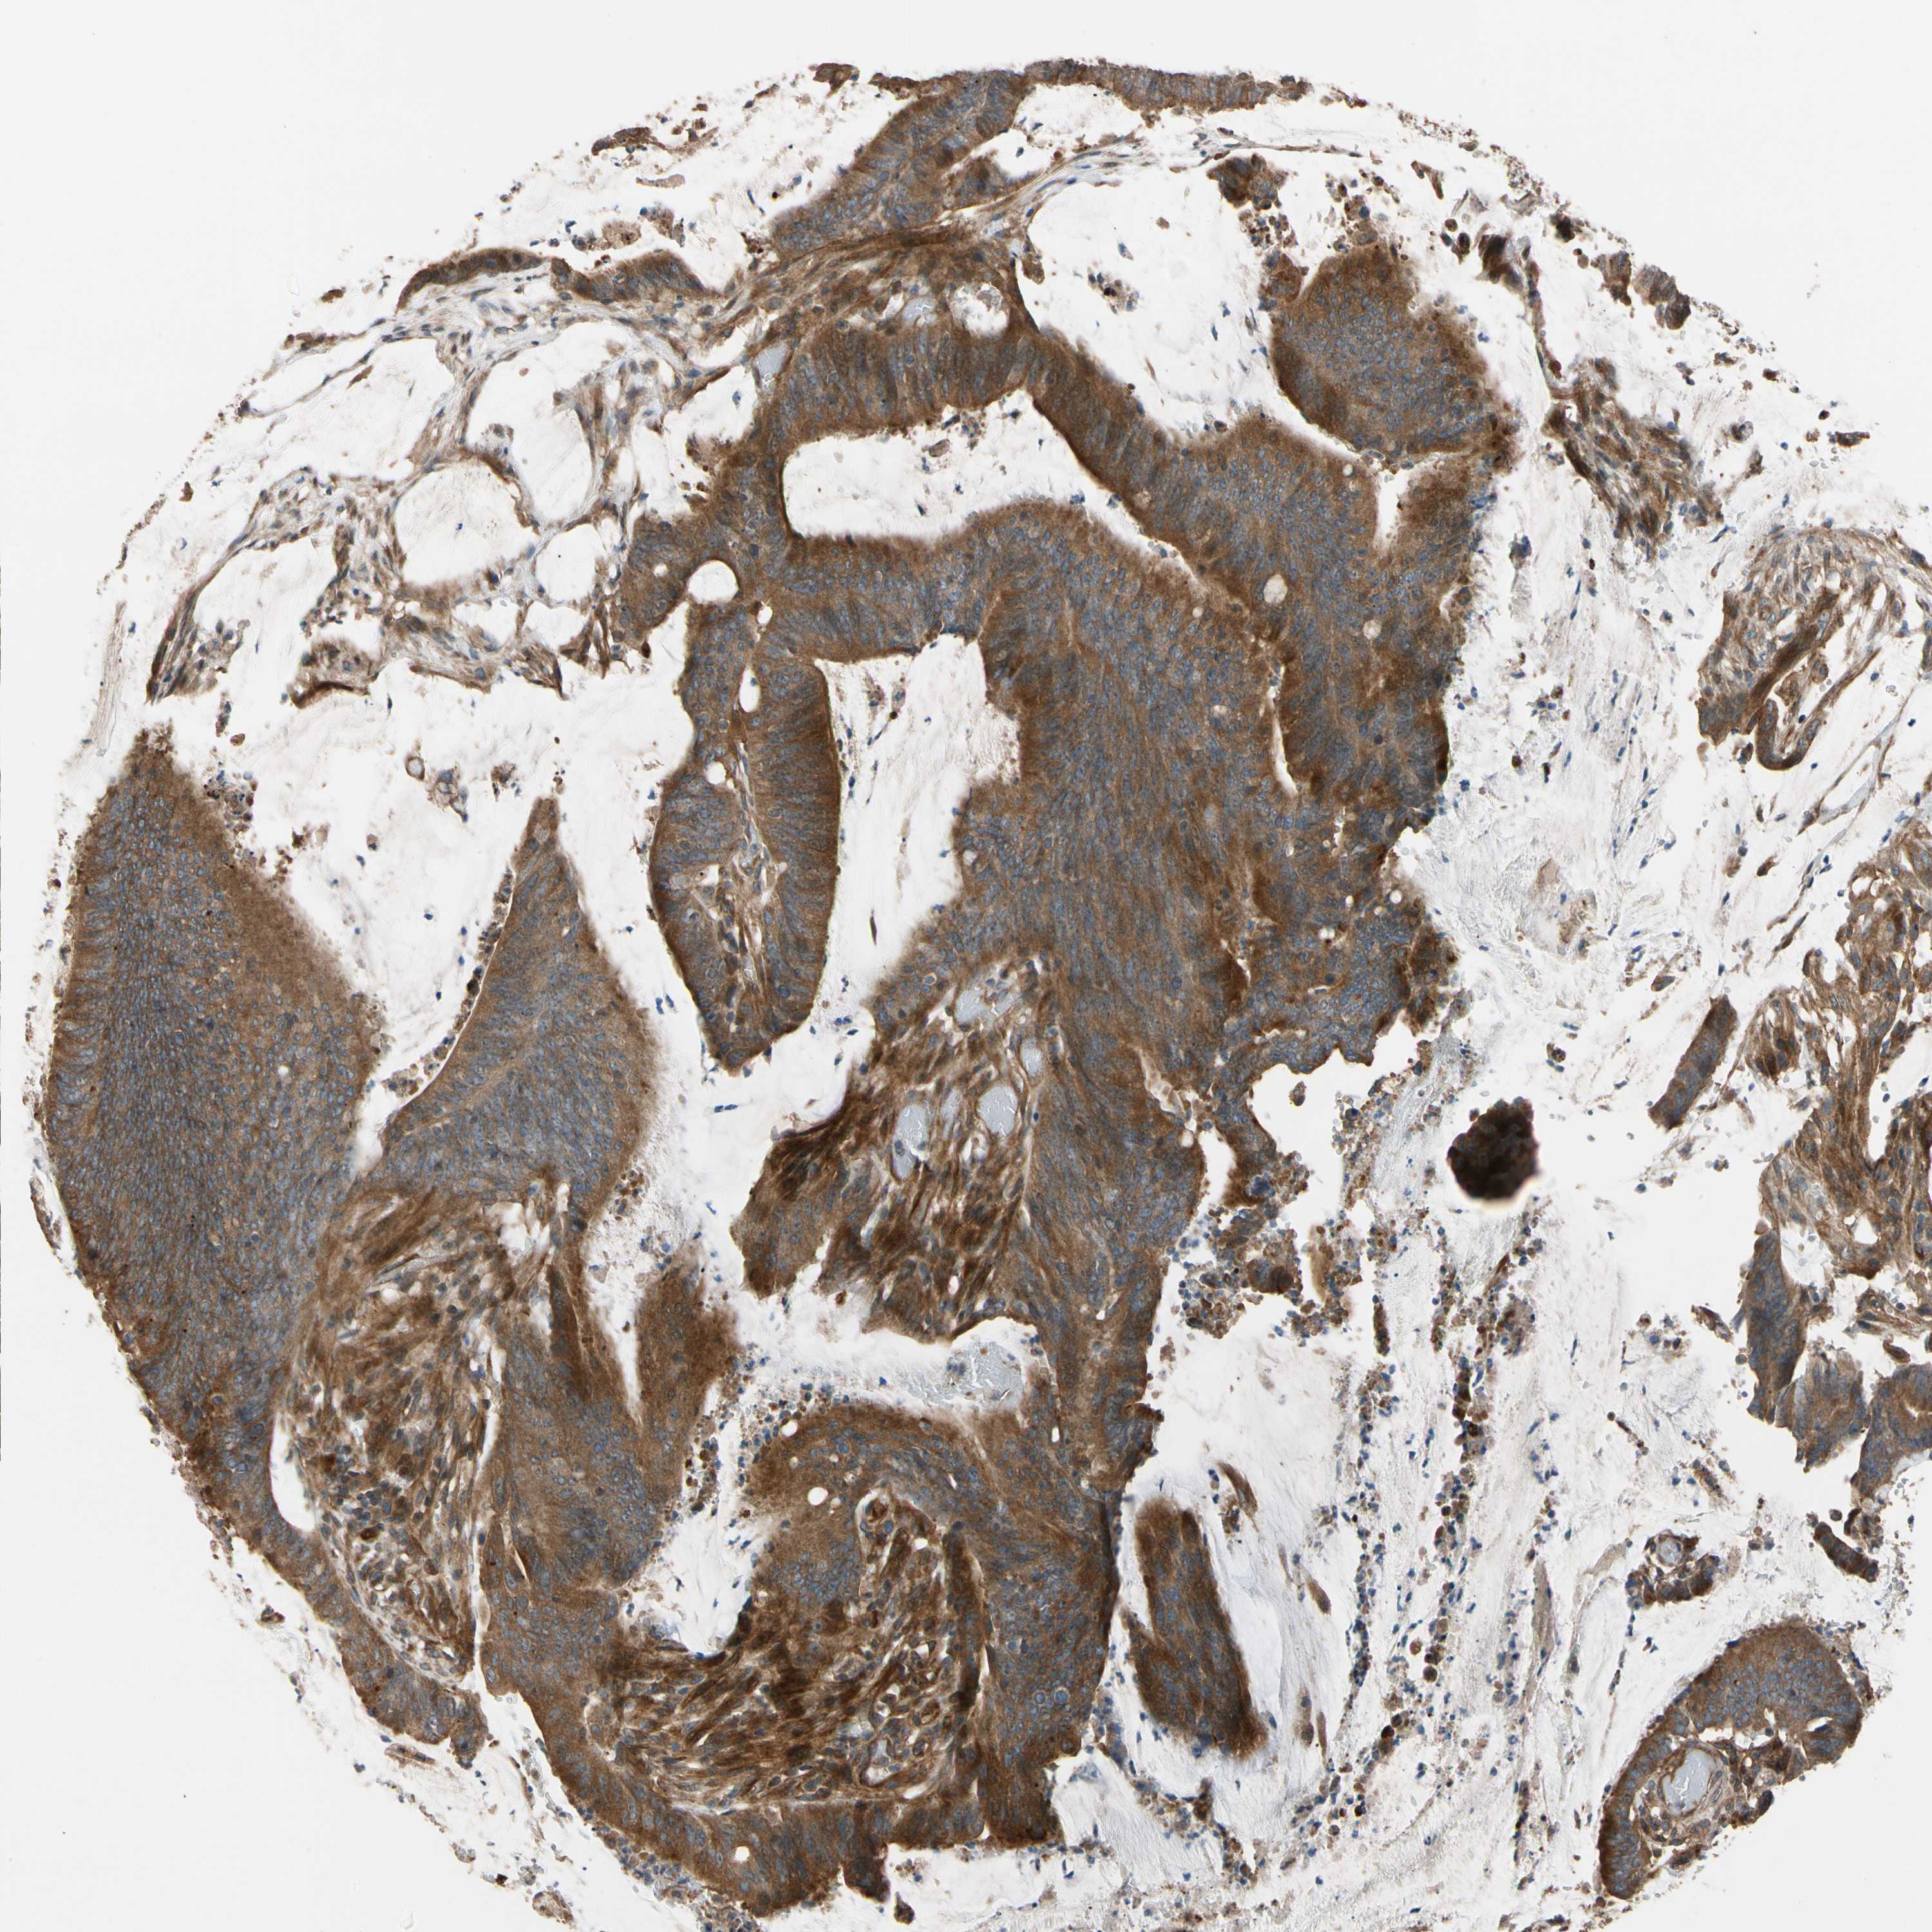

CANCER COLORECTAL CANCER Show tissue menu

Colorectal cancer

Human cancer

Colon adenocarcinoma